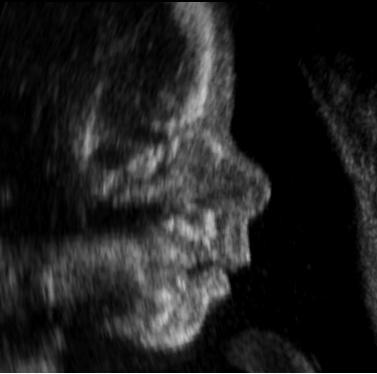

Das Materialblatt „Schwangerschaftsabbruch und Lebensschutz konkret“ behandelt ethische Konflikte rund um Schwangerschaftsabbruch, Pränataldiagnostik und den Schutz menschlichen Lebens. Im Mittelpunkt steht die Fallgeschichte eines Paares, das nach einer künstlichen Befruchtung während der Schwangerschaft mit der Diagnose einer schweren Fehlbildung des ungeborenen Kindes konfrontiert wird. Der Text beleuchtet die Situation aus unterschiedlichen Perspektiven, etwa aus Sicht der Mutter, des Vaters, der behandelnden Ärztin, einer Sozialpädagogin sowie durch ethische Positionen des Philosophen Peter Singer und von Papst Johannes Paul II. Darüber hinaus werden rechtliche Regelungen des österreichischen Strafgesetzbuches zum Schwangerschaftsabbruch dargestellt. Das Medium verdeutlicht die Spannungen zwischen Selbstbestimmung, Lebensschutz, Verantwortung, medizinischen Möglichkeiten und gesellschaftlichen Wertvorstellungen.